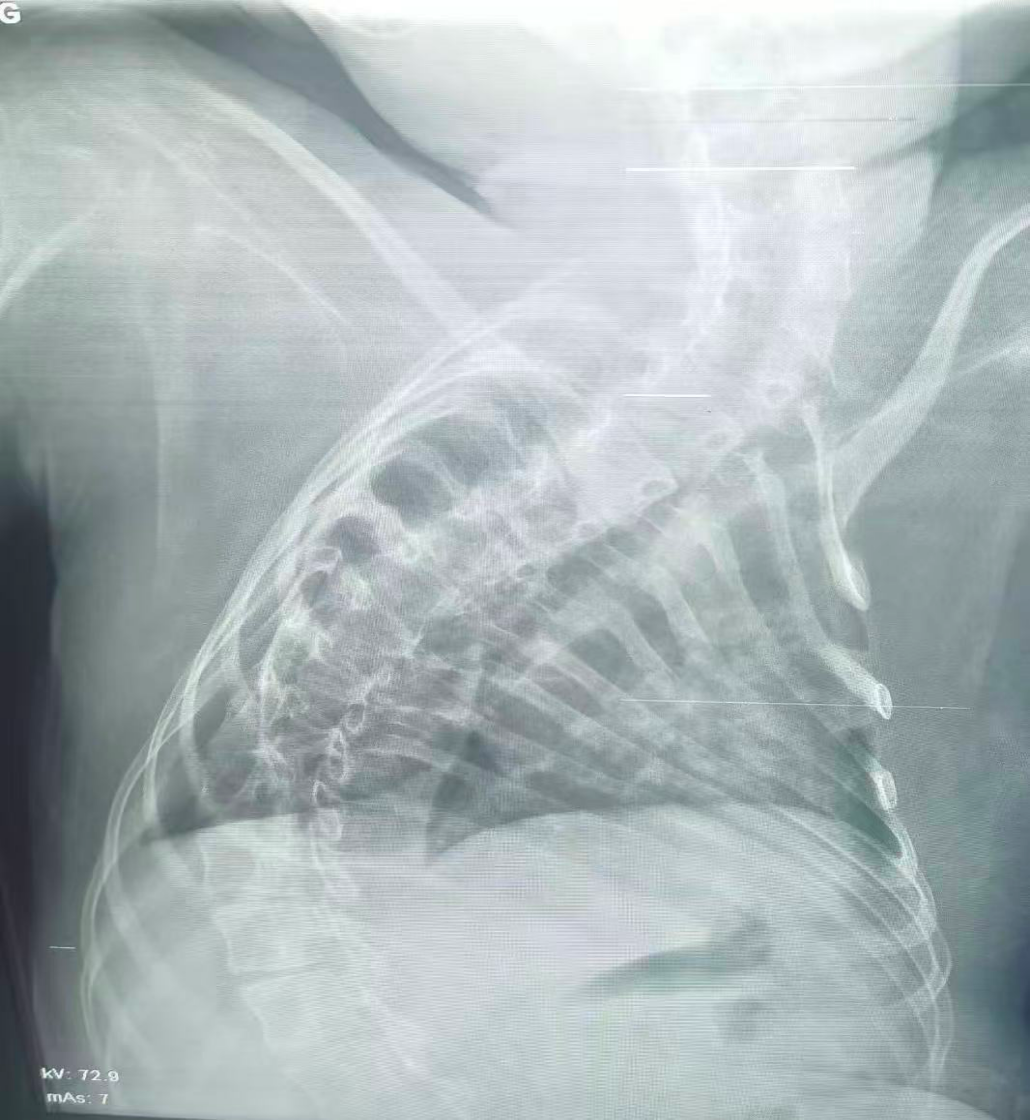

該患兒因患脊髓性肌萎縮癥長期臥床,呼吸肌已嚴重無力,自主呼吸微弱且?guī)缀鯁适Э人耘盘的芰?,此次并發(fā)支氣管肺炎后,肺部感染迅速加重,生命已然懸于一線。更棘手的是,嚴重的脊柱側彎使患兒胸廓畸形、氣道解剖結構明顯移位,常規(guī)纖支鏡進鏡路徑完全失效,扭曲狹窄的氣道如同縱橫交錯的“迷宮”,每一步操作都必須精準到毫米級別。

治療前